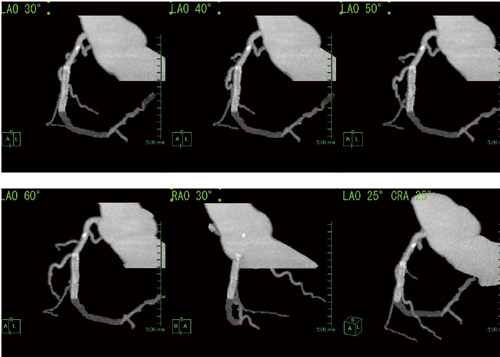

4.冠動脈CTを用いたPCIマッピングの進歩

慢性完全閉塞(CTO)症例に対する経皮的冠動脈インターベンション(PCI)施行時には,末梢の血流が見えないため,より安全に施行するために,CTやMRIによる術前マッピングの有用性が期待されている。PCIを行う際には,以前からCAG like viewが推奨されていたが,細血管の描出が困難で,分枝描出に限界があることが課題となっていた(図3)。そこで,CTOに対するPCI施行時には,3D画像による全体像の把握と,2D画像による閉塞部位の把握を両立できればより有用だが,AZE VirtualPlaceには,2D画像と3D画像を連動させて観察できるモードが搭載されており,より安全にPCIが施行可能となった(図4)。

図3 CAG like viewによるPCIマッピング

図4 2D画像と3D画像を連動させたPCI術前マッピング